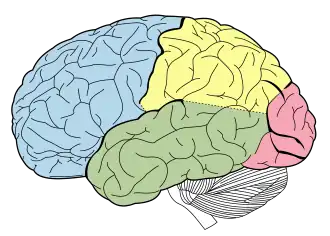

Lobes of the human brain (temporal lobe is shown in green) | |